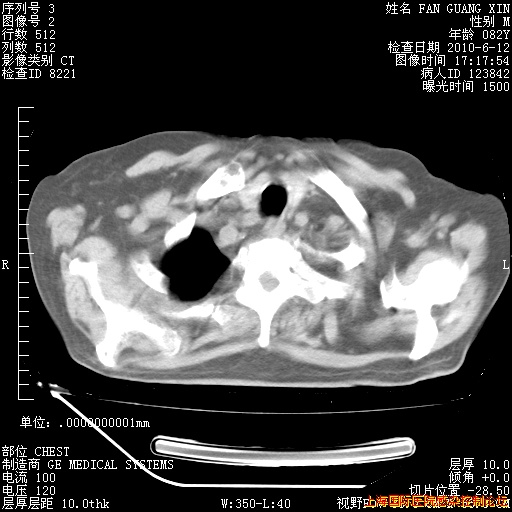

6月12日纵膈窗